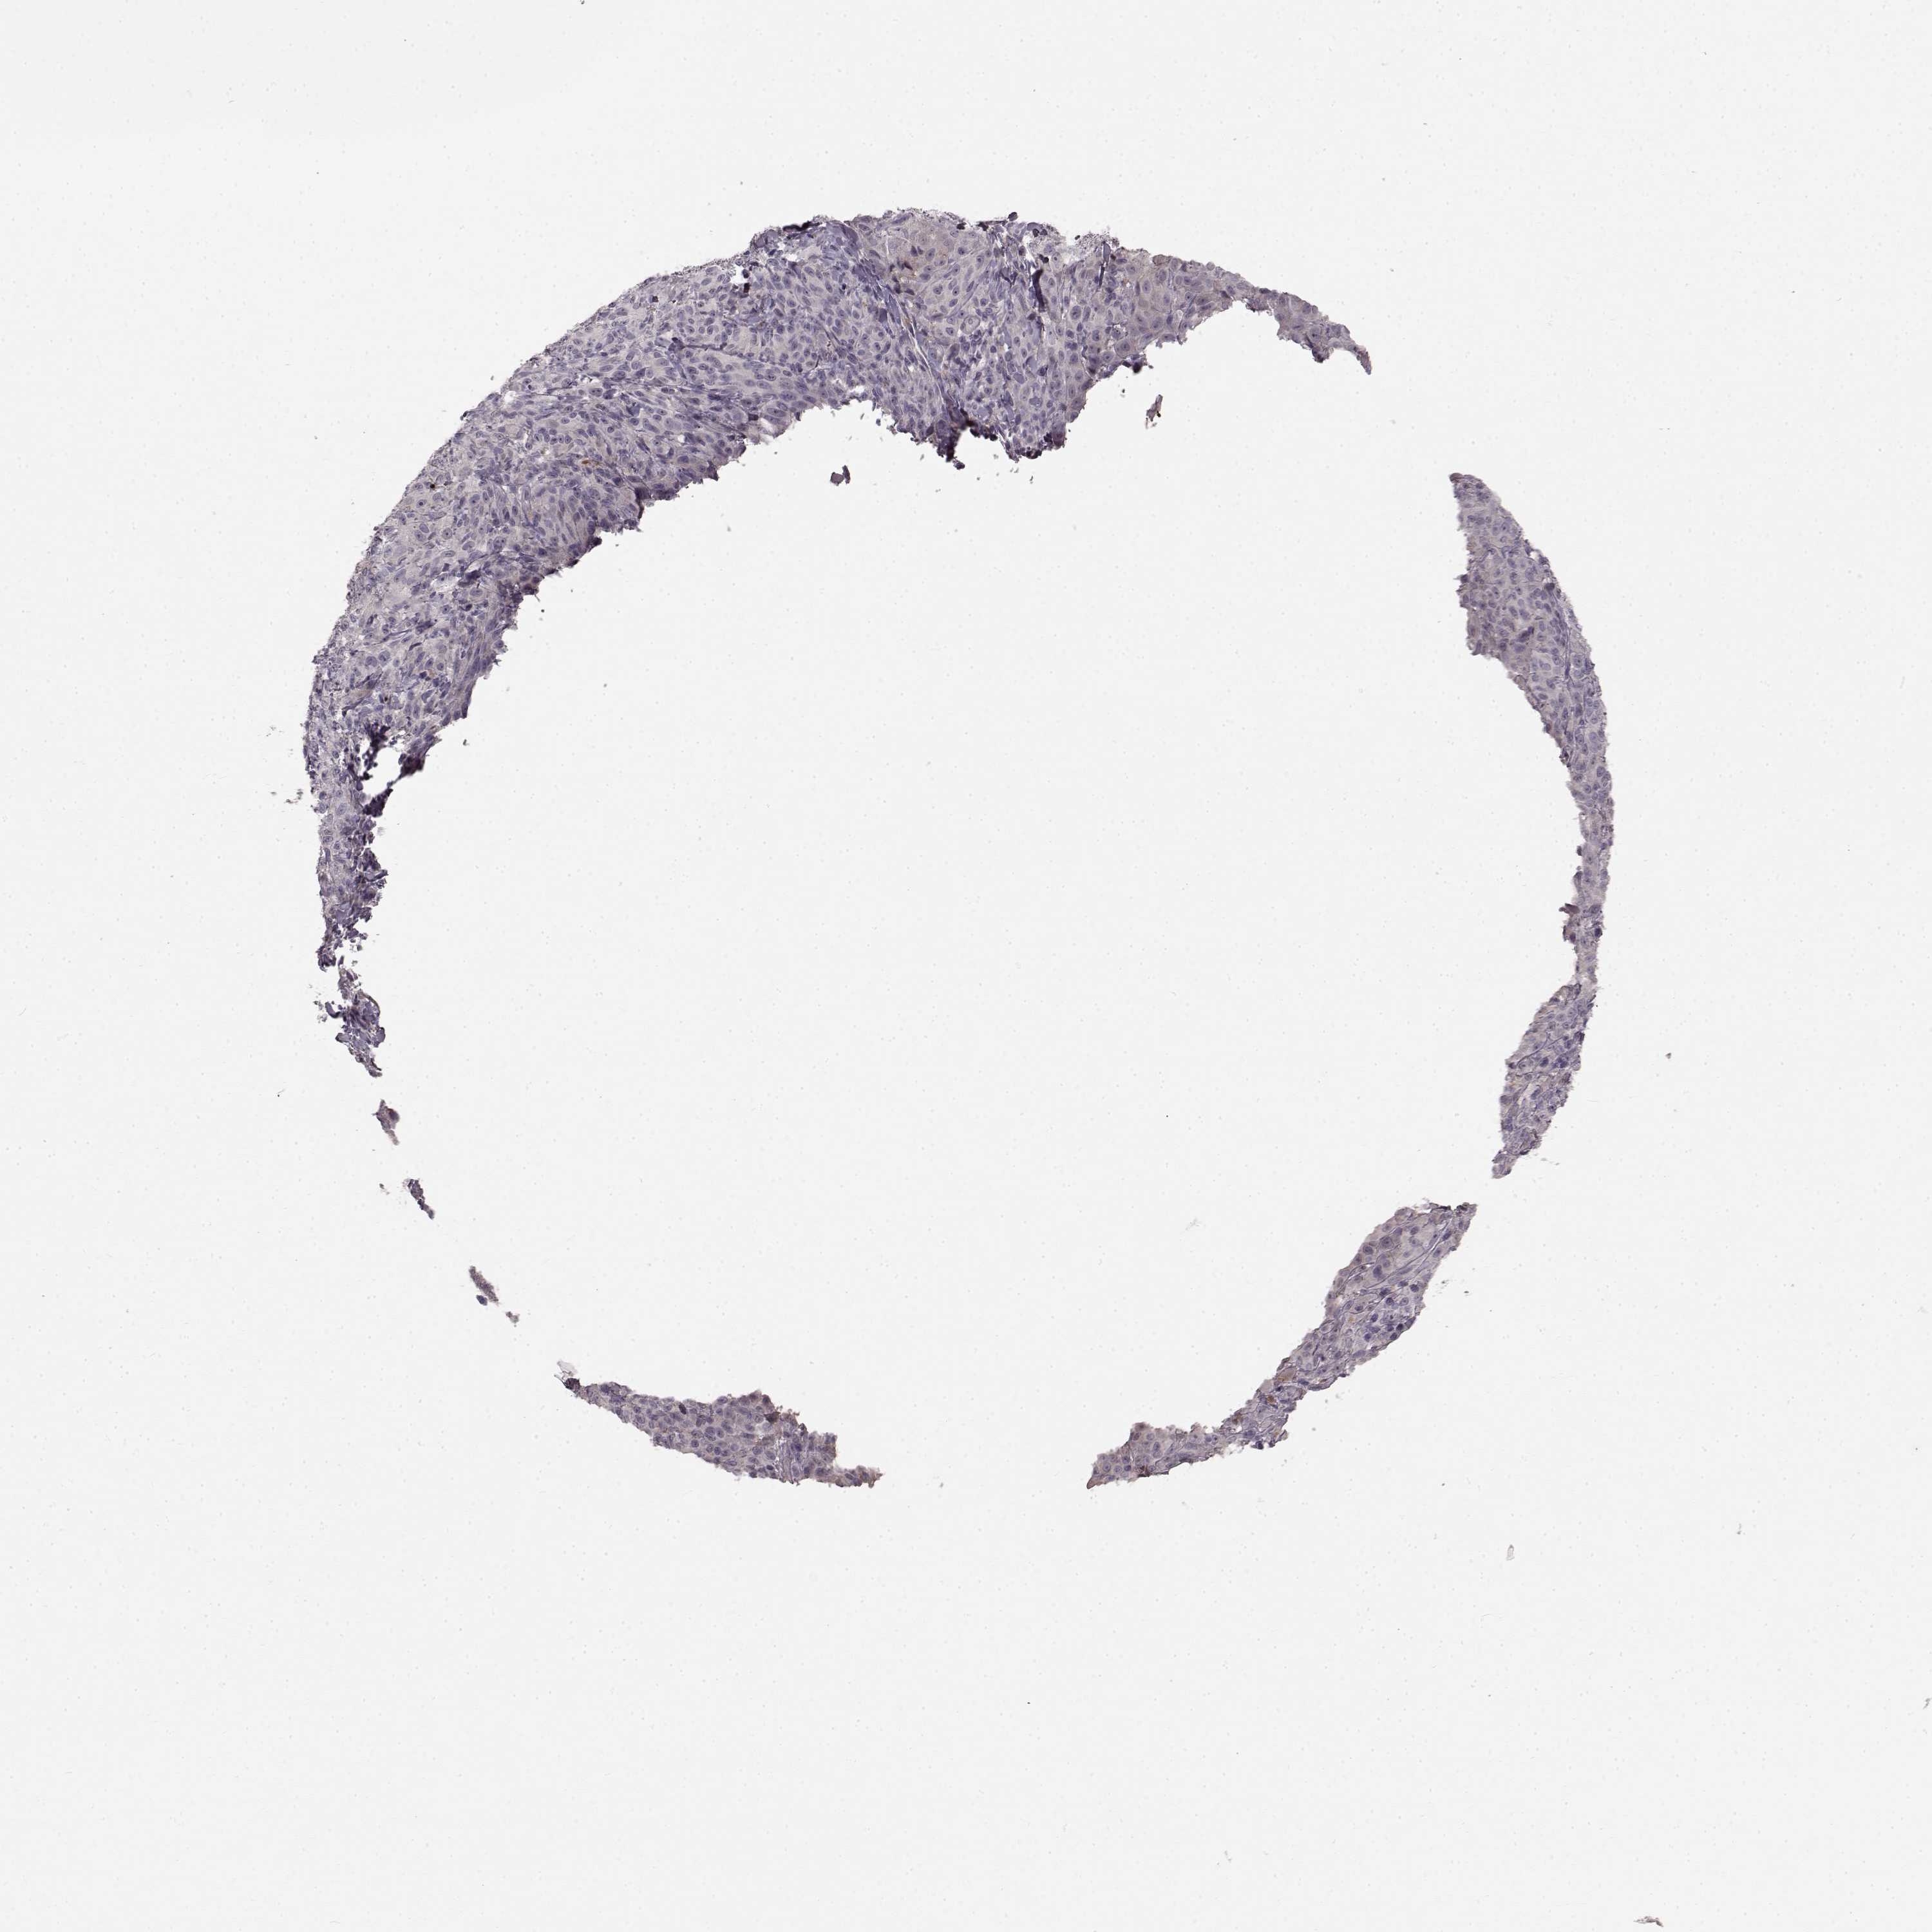

MELANOMA - Protein expressioni

A mouse-over function shows sample information and annotation data. Click on an image to view it in a full screen mode. Samples can be filtered based on level of antibody staining by selecting one or several of the following categories: high, medium, low and not detected. The assay and annotation is described here.

Note that samples used for immunohistochemistry by the Human Protein Atlas do not correspond to samples in the TCGA dataset.

Antibody stainingi

Antibody staining in the annotated cell types in the current human tissue is reported as not detected, low, medium, or high, based on conventional immunohistochemistry profiling in selected tissues. This score is based on the combination of the staining intensity and fraction of stained cells.

Each image is clickable and will lead to virtual microscopy that enables deeper exploration of all samples and also displays staining intensity scores, fraction scores and subcellular localization as well as patient and tissue information for each sample.

Antibody HPA067812

Antibody HPA071461

Staining

High

Medium

Low

Not detected

Intensity

Strong

Moderate

Weak

Negative

Quantity

>75%

75%-25%

<25%

None

Location

Nuclear

Cytoplasmic/membranous

Cytoplasmic/membranous,nuclear

Malignant melanoma, NOS

Malignant melanoma, Metastatic site